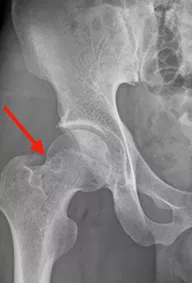

Vol.09[腰痛、右下肢痛(鼠径部から大腿部前面)]

3ヶ月前から誘因なく、腰痛、右下肢痛が出現。疼痛持続し、近医整形外科で腰椎MRIを撮像され、L4/5の腰椎椎間板ヘルニアを指摘され、鎮痛薬開始されたが改善なく、股関節単純X線で大腿骨の透亮像を指摘され、精査加療目的で当科紹介となった。